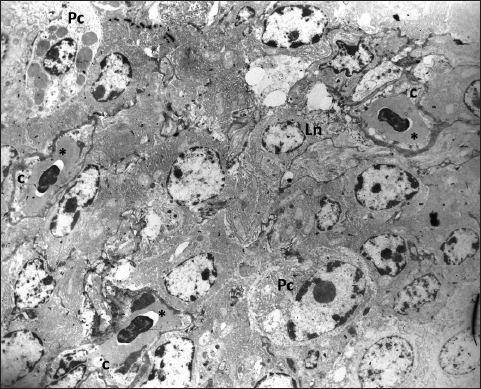

Fig. 5. In the subepithelial region of the primary duct of the Harderian gland is visible one capillary containing two erythrocytes (*). The capillary endothelium (e) is thin and poses fenestra (arrow) TEM; 2880X. Ultrastructural analysis shows that the tissue of the Harderian gland has capillaries with a thin endothelium and occasionally visible fenestrae (Fig. 5). The fenestrated capillaries are identified in the subepithelial region, as well as in the deeper part of the glandular tissue, where they come into close contact with lymphocytes and plasma cells (Figs. 6 and 7). DiscussionDifferent research shows that the structure of the Harderian gland and its function is quite variable among animal species (Olcese and Wesche, 1989; Payne, 1994; Domínguez-Pérez, 2019; Mahmoud et al., 2022; Oliveira et al., 2023). However, the studies regarding the blood supply of this gland still are very limited in all species. In fowls and sparrows (Passer domesticus), it is reported that the Harderian gland receives the arterial supply via the ophthalmotemporal branch of the external ophthalmic artery, while venous blood is collected and drained by the ophthalmic vain (Wight et al., 1971; Payne, 1994). In Nomina Anatomica Avium, these blood vessels are named as aa. and vv. glandulae membranae nictitantis (Baumel et al., 1993). The results of our research partially coincide with these findings. By careful analysis of arterial vascular casts, we identified the one branch that separates from the a. ophthalmotemporalis, but besides this, we also found the second artery that comes from the a. nasalis communis. The branch that separates from the common nasal artery supplies the anterior part of the gland and its primary duct and it is not mentioned in Nomina Anatomica Avium or any previous research (Richards, 1967, 1968; Wight et al., 1971; Baumel et al., 1993; Payne, 1994). Following the course of venous blood vessels, unlike Wight et al. (1971), we identified three veins that drain the gland. Two of them drain the main part of the gland and both inflows separately into the v. ophthalmoteporalis, while the third, enters into the v. nasalis communis. As for arteries, we did not find any data in the present literature regarding the drainage of the gland by the branches of the common nasal vein. In a recently conducted study of cephalic vascularization in turkey and turkey vulture birds, the main intraorbital blood vessels are shown in figures, but the arteries and veins that supply the Harderian gland are not labeled or described in the manuscript (Arad et al., 1989; Porter and Witmer, 2016). Comparing the vascular pattern of this research with our findings we can say that the vascularisation of the gland is very similar between these bird species. Also, comparing the methodology of the research, we can say that both, the corrosive cast technique and CT scanning with the use of contrast media can be equally useful for the display and general study of the distribution of blood vessels, with the fact that CT scanning is practically more convenient and easier to perform. On the other side for fine, ultrastructural research of blood vessels, the use of TEM is still irreplaceable. Ultrastructural research of the Harderian gland conducted on small mammals (common tree shrew and hamster) shows that the gland possesses two capillary types, small fenestrated and irregular sinusoidal (Pradidarcheep et al., 2003; Menendez-Pelaez et al., 2012). Our research by TEM shows that the gland in hens possesses only fenestrated capillaries and this confirms the previous findings of Wight et al. (1971).

Fig. 6. The fenestrated capillaries (c) containing erythrocytes are present in the stroma of the gland where they are surrounded by lymphocytes (Ln) and mature plasma cells (Pc); TEM, 3000X.